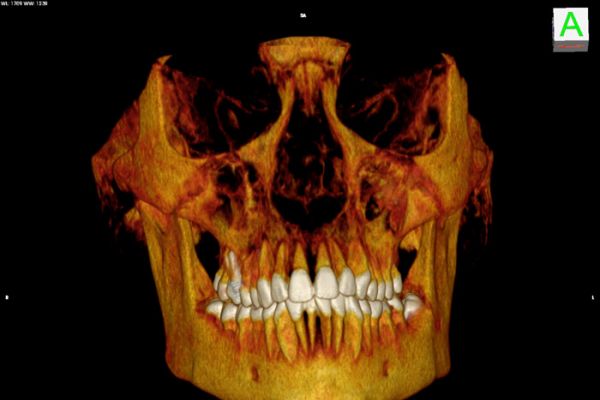

Die Computertomographie ist ein Röntgenverfahren, welches Schnittbilder des menschlichen Körpers erzeugt.

Der Patient liegt auf einer speziellen Untersuchungsliege und wird langsam durch den Detektorring gefahren. Die Röntgenröhre rotiert dabei spiralförmig um einen definierten Körperabschnitt um den Patienten , wobei ein kontinuierlicher Datenblock erzeugt wird mit der Möglichkeit, durch Nachbearbeitung (Rekonstruktionen) Schichtbilder in verschiedenen Ebenen und Schichtdicken, oder ein 3D-Modell der untersuchten Organe (z.B. Knochen, Gefäße) zu erstellen.